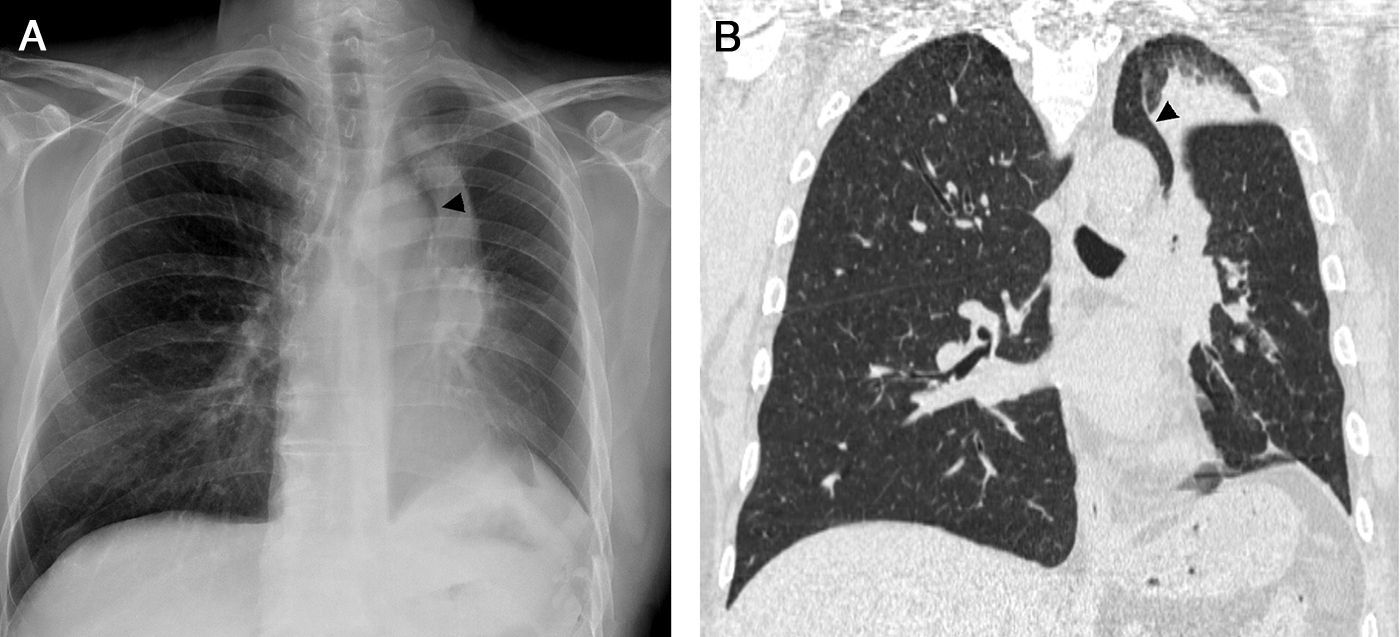

La atelectasia pulmonar es un indicador importante de una enfermedad subyacente, potencialmente grave, que es imprescindible diagnosticar precozmente. Uno de los mecanismos más frecuentes es la reabsorción de aire distal a la obstrucción de las vías respiratorias. La radiografía de tórax es una herramienta excelente para diagnosticarla, especialmente útil para descartar obstrucciones bronquiales centrales (por ejemplo, una neoplasia endobronquial). Si no se reconocen correctamente los signos de la pérdida de volumen el diagnóstico y el tratamiento pueden retrasarse. En este artículo se describen los principales hallazgos radiográficos de la atelectasia pulmonar lobular y su correlación con la tomografía computarizada. Se incluyen los signos clásicos descritos en la bibliografía y otros menos conocidos y a su vez sutiles.

Atelectasis is an important indicator of potentially severe underlying disease that must be diagnosed as early as possible. One of the most common mechanisms is the reabsorption of air distal to respiratory tract obstruction. The chest X-ray is an excellent tool to diagnose atelectasis, and it is especially useful for ruling out central bronchial obstructions (e.g., from endobronchial tumors). If the signs of volume loss are not recognized correctly, the diagnosis and treatment can be delayed. This article describes the main findings of lobar atelectasis on chest X-rays and their correlations with CT findings, including the classic signs described in the literature and other, less known and sometimes subtle signs.